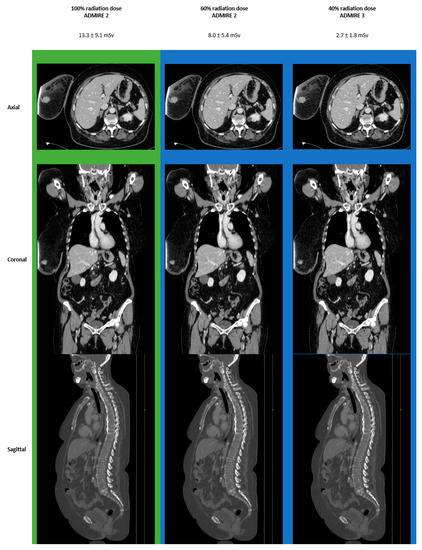

3.4. Images

| 100% | 7.9 ± 1.4 | 14.9 ± 9.8 | 13.3 ± 9.1 | |

| 80% | 6.3 ± 1.1 | 11.9 ± 7.8 | 10.7 ± 7.2 | |

| 60% | 4.7 ± 0.8 | 8.9 ± 5.9 | 8.0 ± 5.4 | |

| 40% | 3.2 ± 0.6 | 6.0 ± 3.9 | 5.3 ± 3.6 | |

| 20% | 1.6 ± 0.3 | 3.0 ± 2.0 | 2.7 ± 1.8 | |